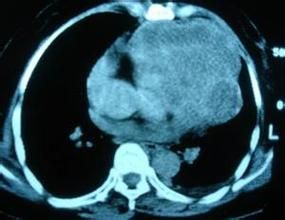

畸胎瘤大多數為外生性或有明顯腫塊可捫及,根據臨床表現常能早期診斷。仔細的腹部體檢和直腸指檢,對腹部、盆腔、隱型骶尾部畸胎瘤的檢查非常必要;腫瘤部位的X線平片可發現腫瘤內有骨、牙齒等異常鈣化影而明確畸胎瘤,並多為成熟型畸胎瘤;胃腸道鋇餐、鋇劑灌腸和靜脈腎盂造影可了解相應部位的胃腸道或腎臟、輸尿管、膀胱等臟器的受壓推移情況。對生長迅速、浸潤範圍較廣的畸胎瘤病例應進行CT、核磁共振檢查,以明確腫瘤浸潤範圍及與重要血管,脊髓神經的相鄰關係。